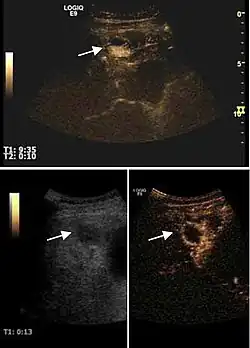

2D ultrasound, Doppler ultrasound and especially CEUS can play an important role in pretherapeutic staging, particularly when sectional imaging investigations (CT, MRI) provide uncertain results or are contraindicated. During the interventional procedure, ultrasound allows guidance of the needle into the tumor. CEUS allows guidance in areas of viable tissue and avoids intratumoral necrotic areas. CEUS also allows assessment of therapeutic effect immediately post-procedure (with the possibility of reintervention in case of partial response) . To accurately assess the effectiveness of treatment it is mandatory to compare the tumor diameter before therapy with the ablation area. The volume of damaged tissue must be higher than the initial tumor volume. CEUS appearance is that of central nonenhanced area showing a peripheral homogeneous hyperenhanced rim due to post-procedure inflammation. 24 hours after the procedure the inflammatory peripheral rim is thinning and the necrotic area appears larger than at the previous examination. Thus, a possible residual tumor may appear more evident. Residual tumor has poorly defined edges, irregular shape, and the tumor diameter is unchanged. Residual tumor tissue is evidenced at the periphery of the tumor as an eccentric area behaving as the original tumor at CEUS examination, with arterial hyperenhancement and portal and late wash-out. Ultrasound examination 24 hours after the procedure, including CEUS, can show apart from the character of the lesion any potential post-intervention complications (e.g. active bleeding).

In the first days after RFA both CEUS and spiral CT have low sensitivity in assessing therapeutic efficacy. CT sensitivity 24 hours post-therapy is reported to be even lower than CEUS. Difficulties in CEUS examination result from post-lesion hyperemia, presence of intratumoral air, ultrasound limitations (too deep lesion or the presence of fatty liver) or lack of patient's cooperation (immediately after therapy). For this reasons contrast imaging (CT or CEUS) control should be performed one month after ablation to confirm the result of the therapy.

Local recurrence is defined as recurrence of a hyperenhanced area at tumor periphery in the arterial phase, with portal and late wash-out. Sometimes, especially for HCC treated by alcoholization (PEI) hyperenhanced septa or vessels can be shown inside the lesion.